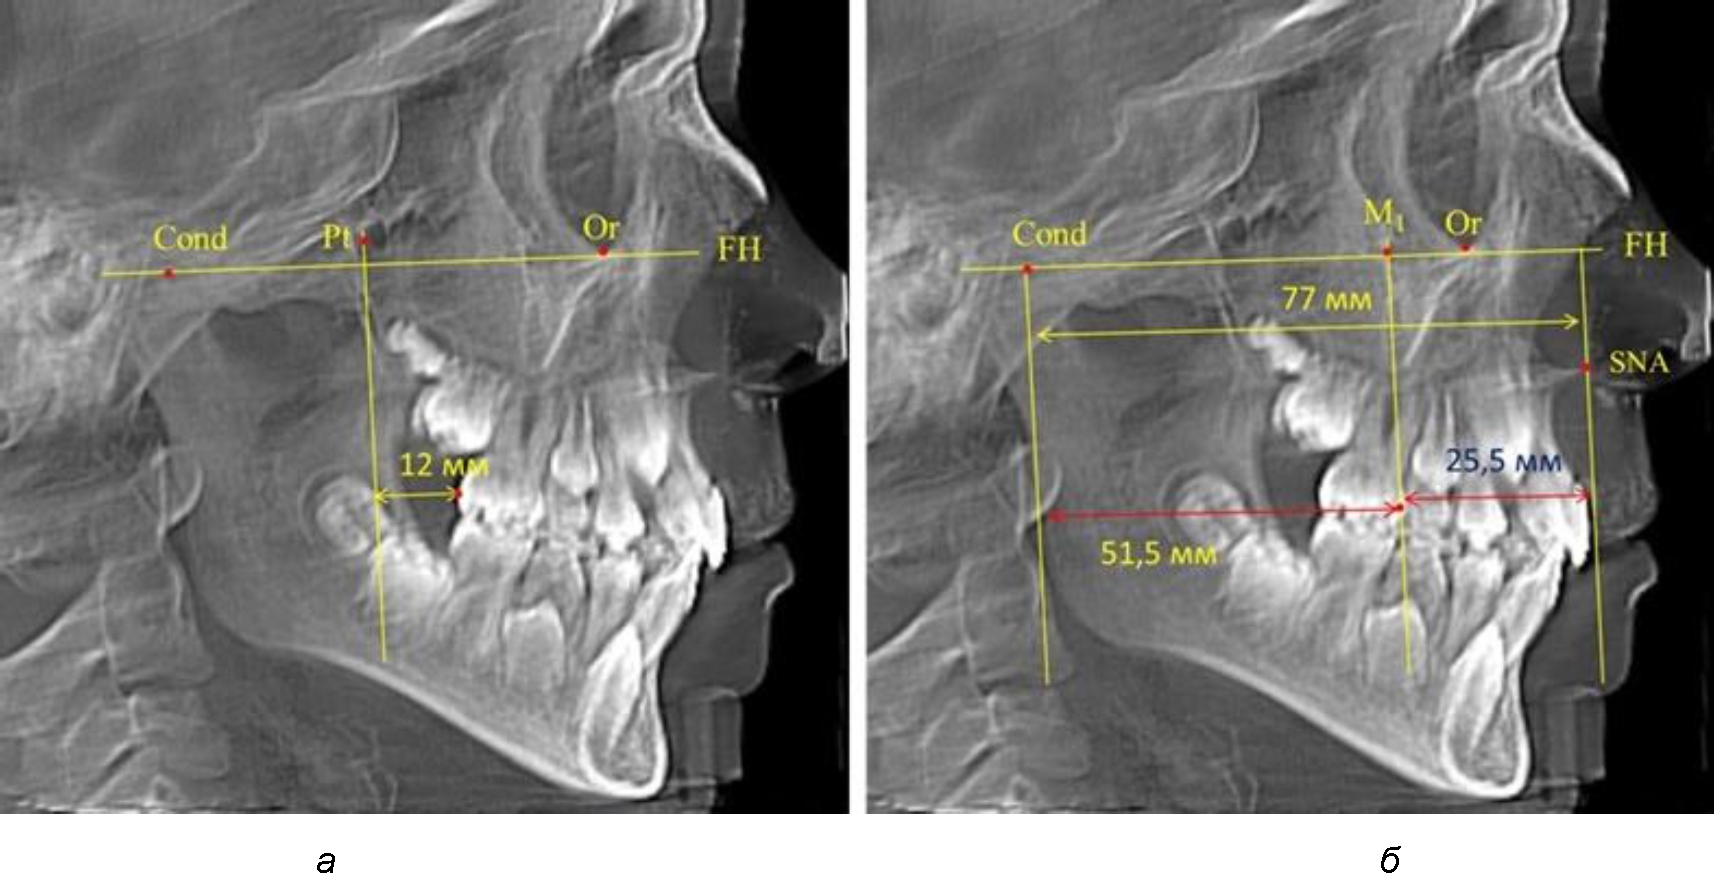

По мере роста челюстей увеличивалась глубина гнатического отдела лица, и кондиллярно-спинальный размер составлял в среднем (74,57 ± 0,93) мм. Дистальная поверхность первого постоянного моляра отстояла от крыловидной вертикали на величину, составляющую около 11 мм, что, так же, как и в периоде прикуса молочных зубов, было близким по значению к данным R. E. McDonald, а именно возраст, плюс 3 мм. Однако величина ошибки среднего значения свидетельствовала о вариабельности признака даже в восьмилетнем возрасте после замены передней группы зубов и установки ключевых постоянных моляров в окклюзионное равновесие. Обращает на себя внимание отношение глубины гнатического отдела лица к дистальному отделу, а именно к кондилярно-молярному расстоянию (рис. 5).

Рис. 5. Особенности положения первых моляров по R. E. McDonald (а) и по предложенному методу (б) у ребенка 8 лет